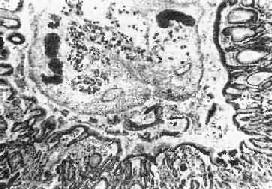

图19-13 肝华支睾吸虫病 胆管内可见虫体,胆管粘膜有腺瘤样增生及炎症 成虫在肝内胆管寄生,使胆管内胆汁淤积,容易发生继发感染。死亡的虫体、虫卵和脱落的胆管上皮还可以成为胆石的核心,促进胆石形成。 关于华支睾吸虫感染与肝癌(胆管上皮癌)的关系,我国病理学者侯宝璋、秦光煜等曾分别对人体或自然感染的动物(家猫及家犬)进行了观察研究,证实在华支睾吸虫感染的致的胆管上皮腺瘤样增生的基础上,可以发生癌变,在人工感染的家猫实验中也得到证实。至于致癌因素是成虫在胆管内蠕动的机械性刺激或虫体代谢产物和胆汁成分的化学刺激,尚有待进一步研究。 2.胆囊 成虫也可在胆囊内寄生(约占9%),镜下可见胆囊壁有嗜酸性粒细胞及淋巴细胞浸润,而上皮细胞增生多不明显。 3.胰腺 成虫也可在胰腺导管内寄生(占6%~37.5%)引起病变,可能是成虫随胆汁进入胰管,也可能是童虫进入胰管内发育为成虫所致。肉眼观,胰管扩张、增厚。镜下,可见胰管上皮增生,并伴有不同程度的鳞状化生(可达95%)。鳞状化生的程度往往与感染的虫数有关。胰腺实质一般无明显改变,但有报告谓可诱发急性胰腺炎。

第三节 华支睾吸虫病华支睾吸虫病(clonorchiasis sinensis)是由华支睾吸虫(clonorchis sinensis)成虫寄居引起,因其主要寄生在肝内胆管,故俗称为肝吸虫病。本病流行于印度、越南、菲律宾等东南亚国家和中国、日本、朝鲜等国。在我国,广东及台湾为主要流行区,但北方各省也有流行区或散发的报告。根据1975年湖北江陵西汉古尸及1994年荆门战国古尸研究,在死者肠内容物内均发现本虫虫卵,说明本病在我国存在至少已有2300多年历史。 【病因及感染途径】 含有成熟毛蚴的虫卵随人或狗、猫和猪等终宿主的粪便入水后,可被第一中间宿主淡水螺吞食,在其消化道内,虫卵内的毛蚴顶开卵盖脱壳而出,并逐渐发育为尾蚴。尾蚴自螺体逸出后在水中游动,遇到第二中间宿主淡水鱼或淡水虾时,在其体内,尤其是肌肉内发育为囊蚴。 当人或动物食入未经煮熟的含活囊蚴的鱼或虾后,囊蚴经胃肠消化酶及胆汁的作用,在十二指肠内脱囊而发育成童虫。童虫经总胆管至肝内胆管寄生并发育为成虫。从食入囊蚴至粪便中出现虫卵约需1个月。 【病变及合并症】 被成虫寄生的肝内胆管,其病变程度因感染轻重而异,轻者感染虫数十余条至数十条,无明显肉眼病变。重度感染常达数千条以上,充满肝内、外胆管,在胆总管、胆囊及胰导管内也可见到。病变的发生除与虫体的机械性阻塞及代谢或崩解产物的化学刺激有关外,虫体产生的抗原所引起的过敏反应也起一定作用。 1.肝 肉眼观,肝轻度肿大,尤以左叶为著,严重时在左叶被膜下即可见到因成虫机械阻塞而扩张的胆管分支,可能因左叶胆管较平直,易被童虫侵入之故。切面见肝内大、中胆管呈不同程度扩张和管壁增厚,胆管的直径可达3~6mm,壁可厚达0.5~3mm(图19-12)。胆管腔内充满胆汁,并含有数目不等的成虫。华支睾吸虫前端较细,后端钝圆,形似葵瓜子,虫体长约10~25mm,宽约3~5mm,柔软而半透明。在有大量虫体寄生的病例,解剖时轻压肝脏,即可见成虫由各胆管中鱼贯而出。镜下,根据感染虫数和感染持续时间的不同,病变可轻重不等。肝内胆管扩和,胆管上皮细胞呈不同程度增生,严重者上皮向管腔内呈乳头状增生,并可在粘膜下见多量的增生腺体,形成腺瘤样结构(图19-13)。上皮细胞还常发生杯状细胞化生而分泌大量粘液。管壁有不等量淋巴细胞、浆细胞和嗜酸性粒细胞浸润。慢性病例则伴有明显的纤维结缔组织增生。部分病例汇管区的结缔组织也呈轻度增生,伴有上述炎性细胞浸润。在急性反应时汇管区的小胆管周围也可有多量嗜酸性粒细胞浸润,而肝实质细胞一般无明显改变。